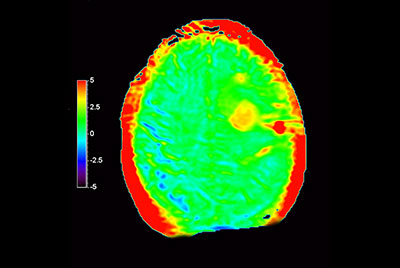

Myocardial infarction with T1/T2 Mapping